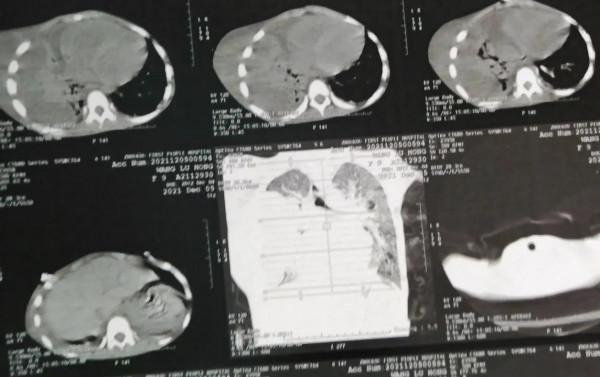

病史簡述:前段時間接診一個9歲的先天聾啞女孩,因咳嗽,咳痰,發熱半月急診轉入我們醫院,自訴在當地醫院輸液未見好轉,胸壁有破潰,膿液外溢!紗布覆蓋,胸部CT可以清晰看出胸腔內外,皮下胸壁都是大量積液,考慮膿液!

診療經過:入選初步診斷考慮膿胸、胸壁膿腫,合併胸壁瘻,經過積極充分引流,加強抗感染治療,複查胸部CT,積液基本引流乾淨,病情也明顯好轉,因後續需長時間住院,考慮經濟及顧及家庭原因,家屬要求並轉當地繼續治療……